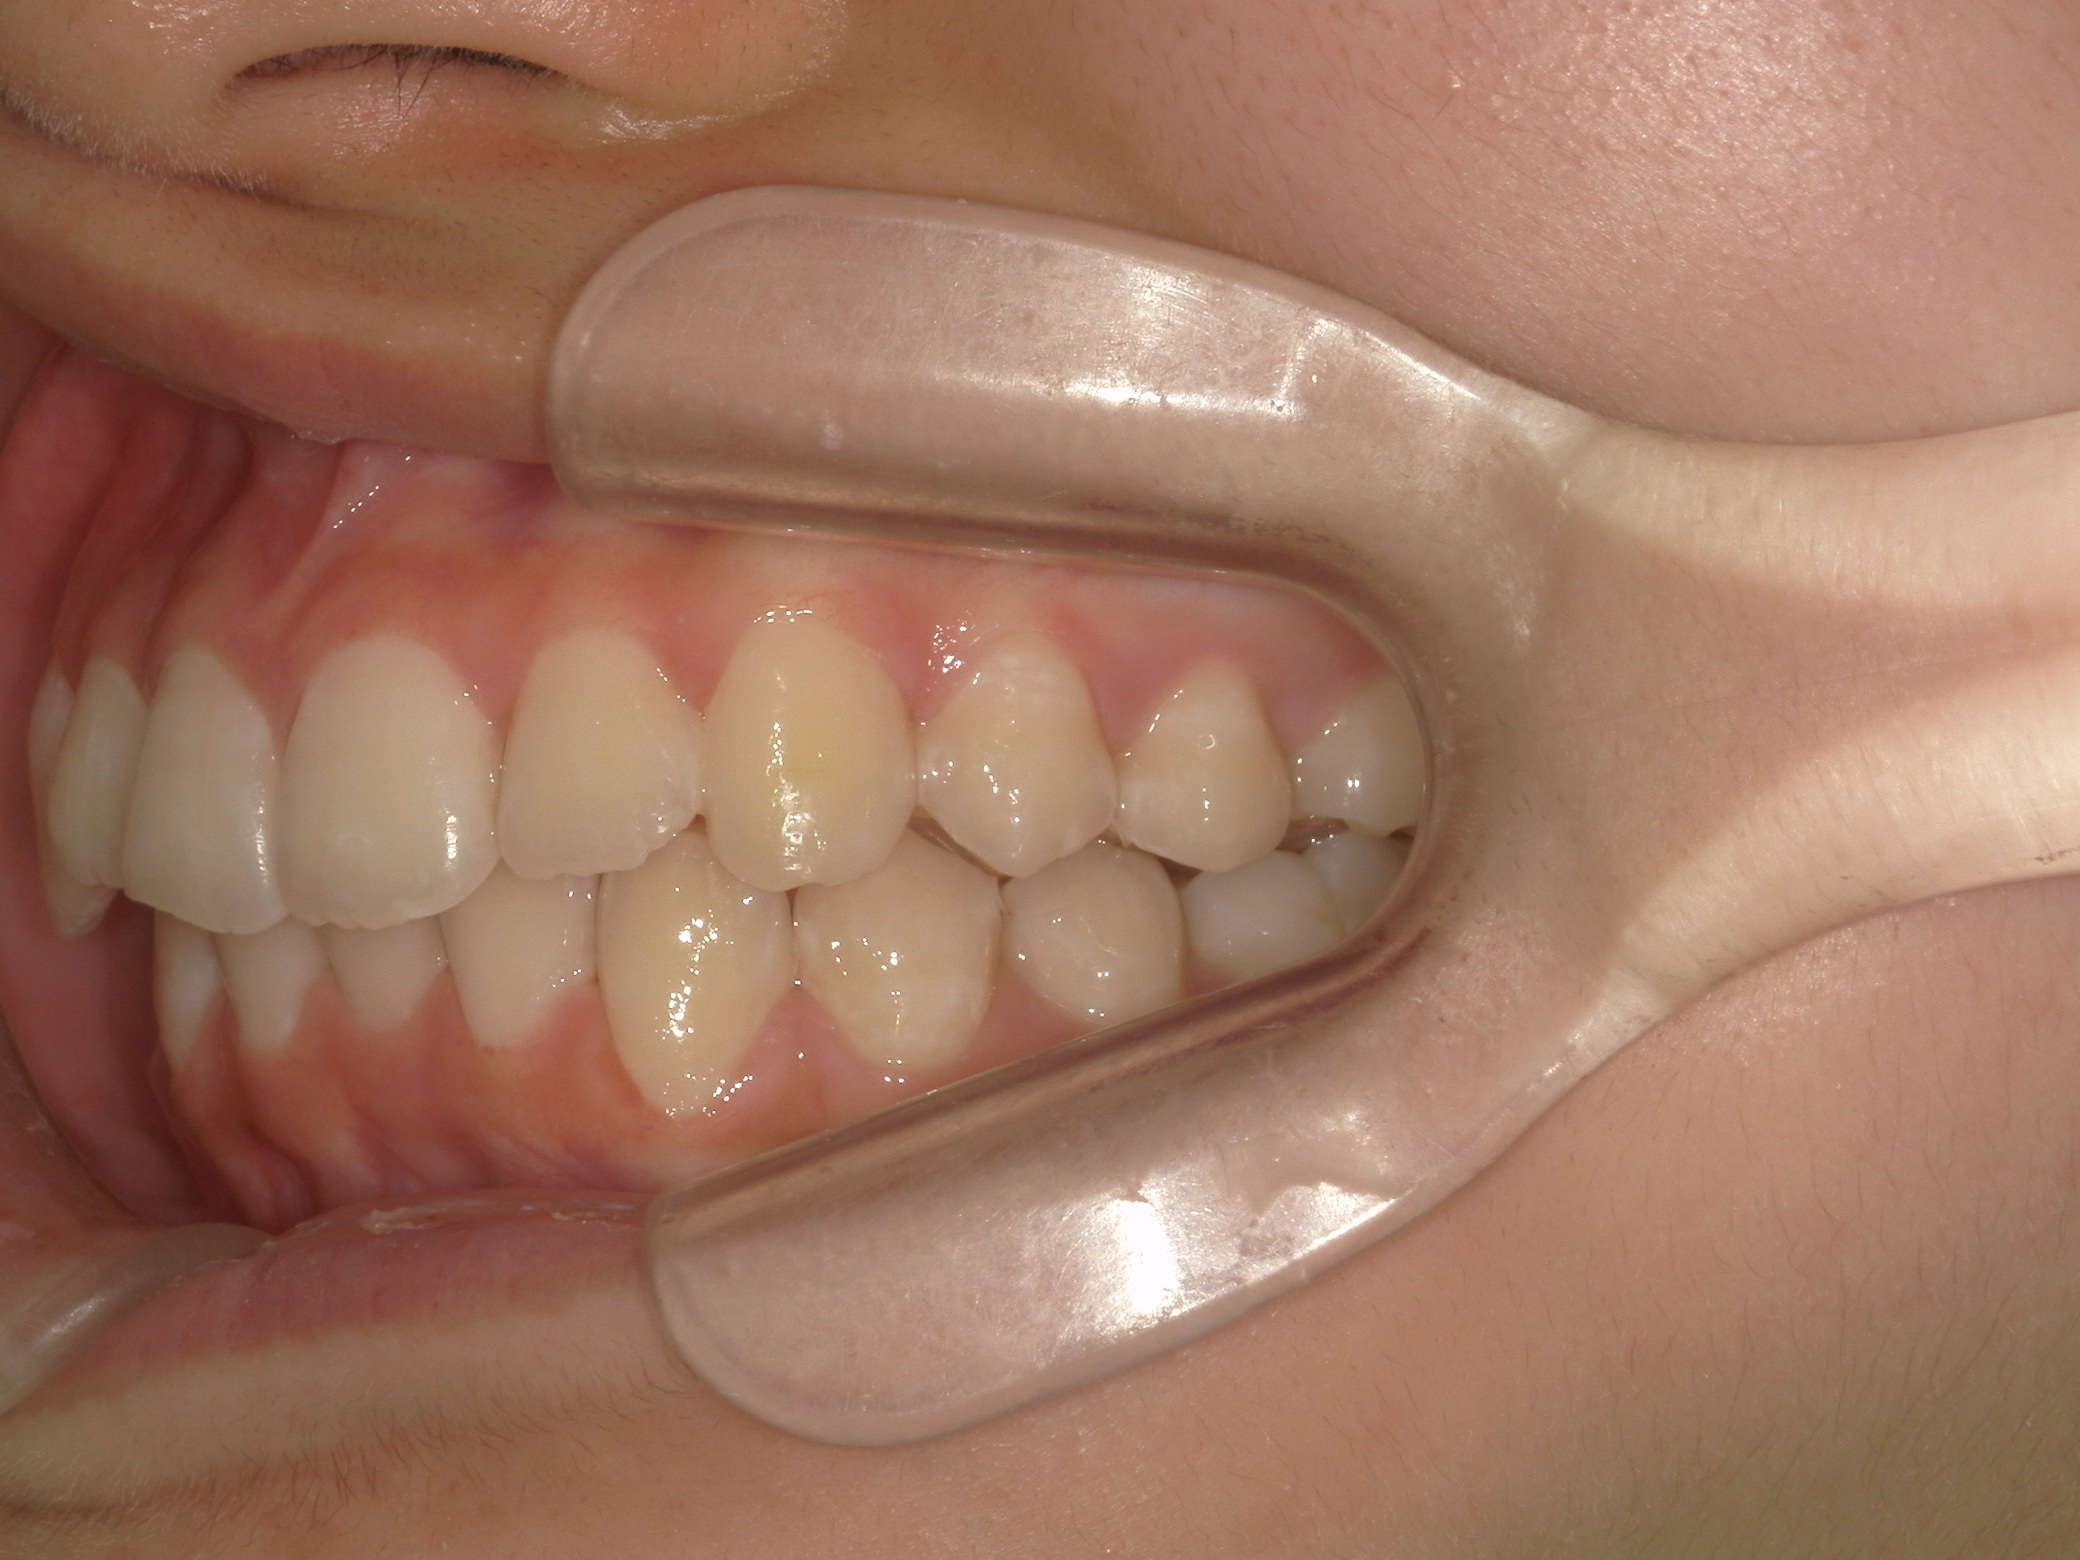

【中学生】インビザラインフル 上顎前突(出っ歯)と 叢生(でこぼこ) を改善

小学生で開始

インビザライン フル

でこぼこ

出っ歯

過蓋咬合

非抜歯

2期治療のみ

Before

After

治療期間

2年

治療開始

14歳

種類

インビザライン矯正

使用装置

インビザラインフル

コメント

先天欠損歯がある患者さんです。

途中 留学されたので 治療を進める速さを遅くした時期もありました。

しっかりはめてくれて 奥歯の咬み合わせも改善し治っています。